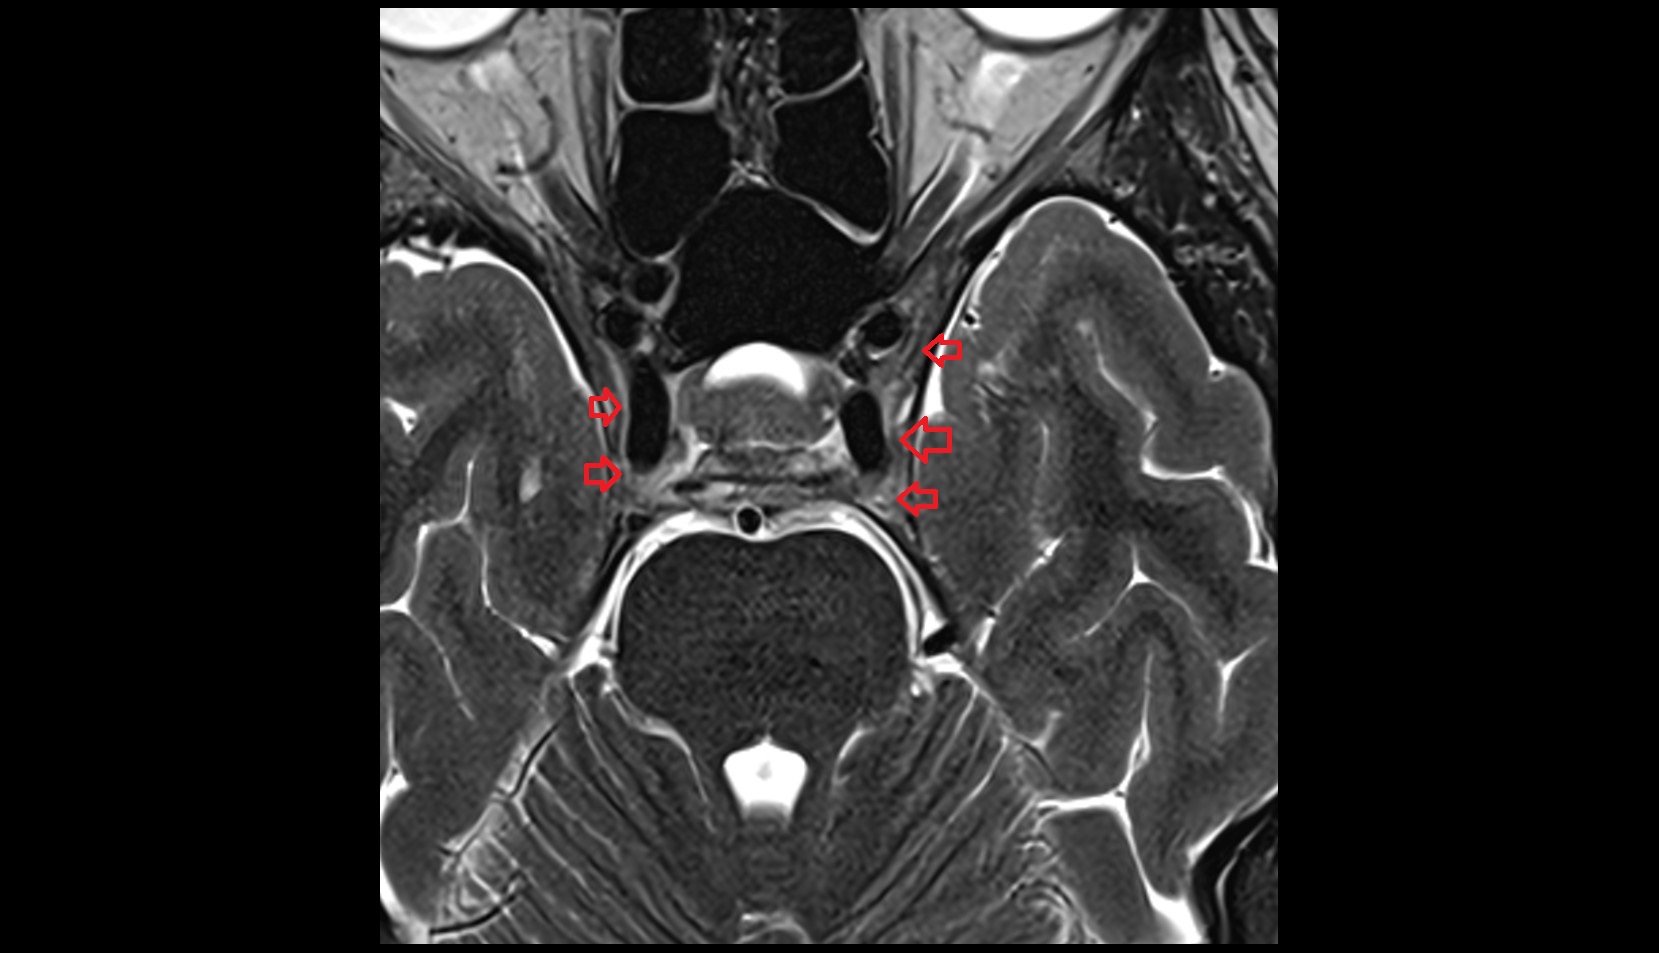

- Exit foramina